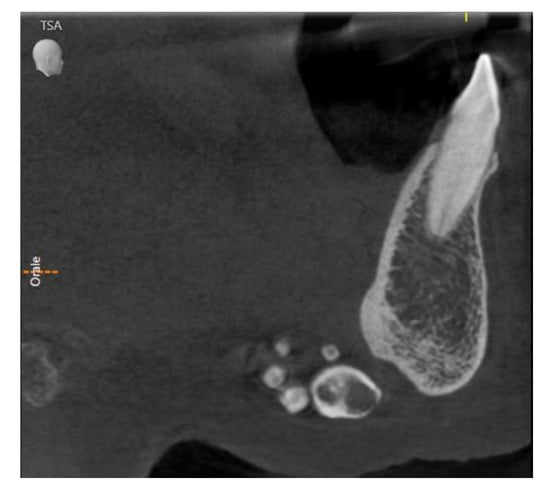

2. Case Presentation